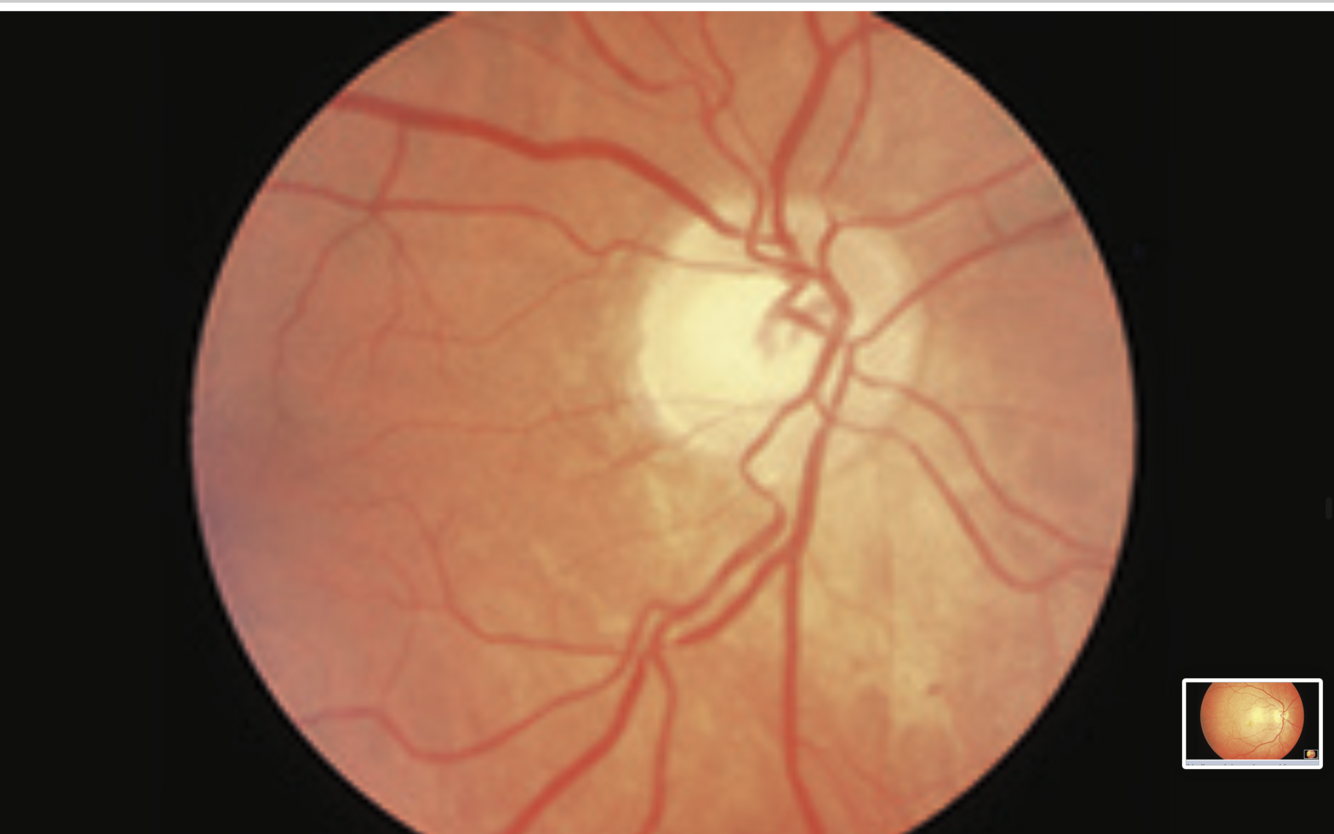

glaucoma

- large cup disc ratio >0.5 = optic disc cupping

- nasal displacement